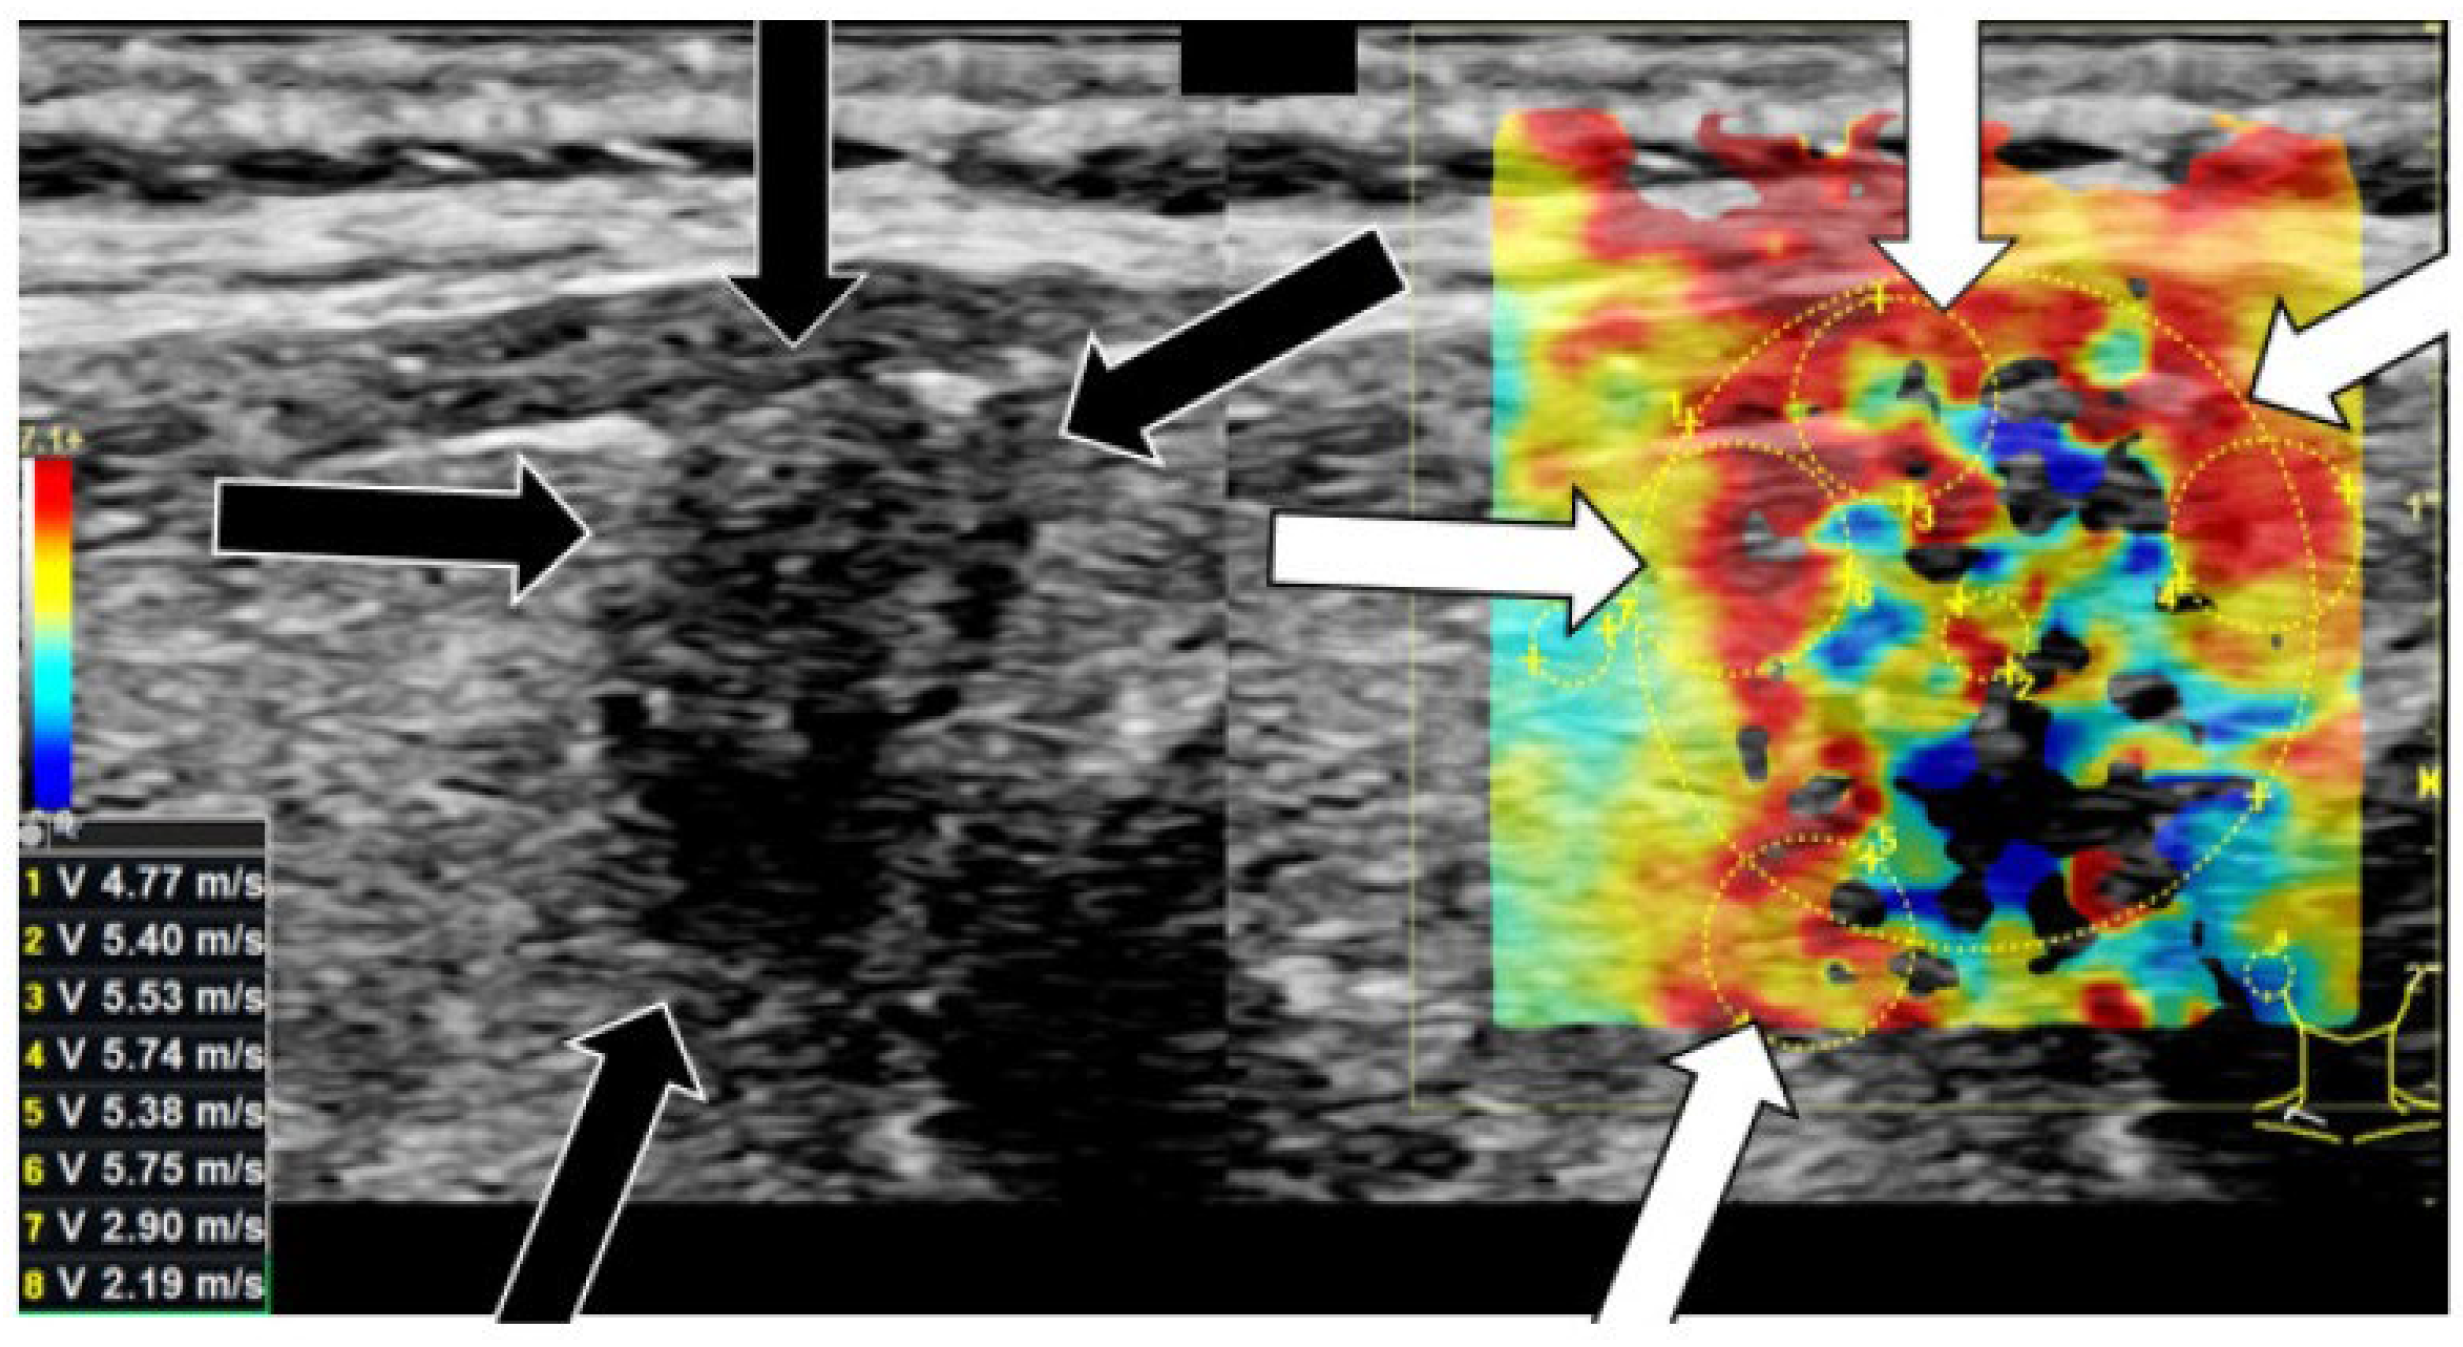

US elastography or shear-wave elastography is a US-derived technique that can differentiate between malignant and benign thyroid nodules based on the elasticity of the tissue [76]. This is a medical imaging modality that maps out the elasticity and stiffness of soft tissues (Figure 17). Elasticity properties provide the clinician with diagnostic information, building on the premise that stiffness is correlated to the presence of abnormalities or disease in the tissue. Initially, elastography was employed to determine the presence of scar tissue or fibrosis in the liver [124]. However, in recent years, this method has been used more frequently to differentiate between thyroid and thyroid nodule malignancy.

Figure 17.

Right thyroid lobe with DTC: Image visualized to differentiate between shear-wave elastography [m/s] (in colors) and B-mode ultrasound (black and white). Arrowheads pointing at irregular hard areas. Adapted from [130], under CC BY-NC 4.0 (Deed—Attribution 4.0 International—Creative Commons).